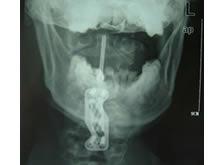

枢椎齿状突骨折并非少见,在成人颈椎骨折脱位中占10%~15%,不幸的是,仍不时有齿状突骨折在首次就诊时被漏诊的报道。任何外伤后出现颈部持续疼痛和僵硬,伴或不伴神经压迫症状的患者,应当给予反复的X线检查。包括CT检查,以免可能的齿状突骨折遗漏。